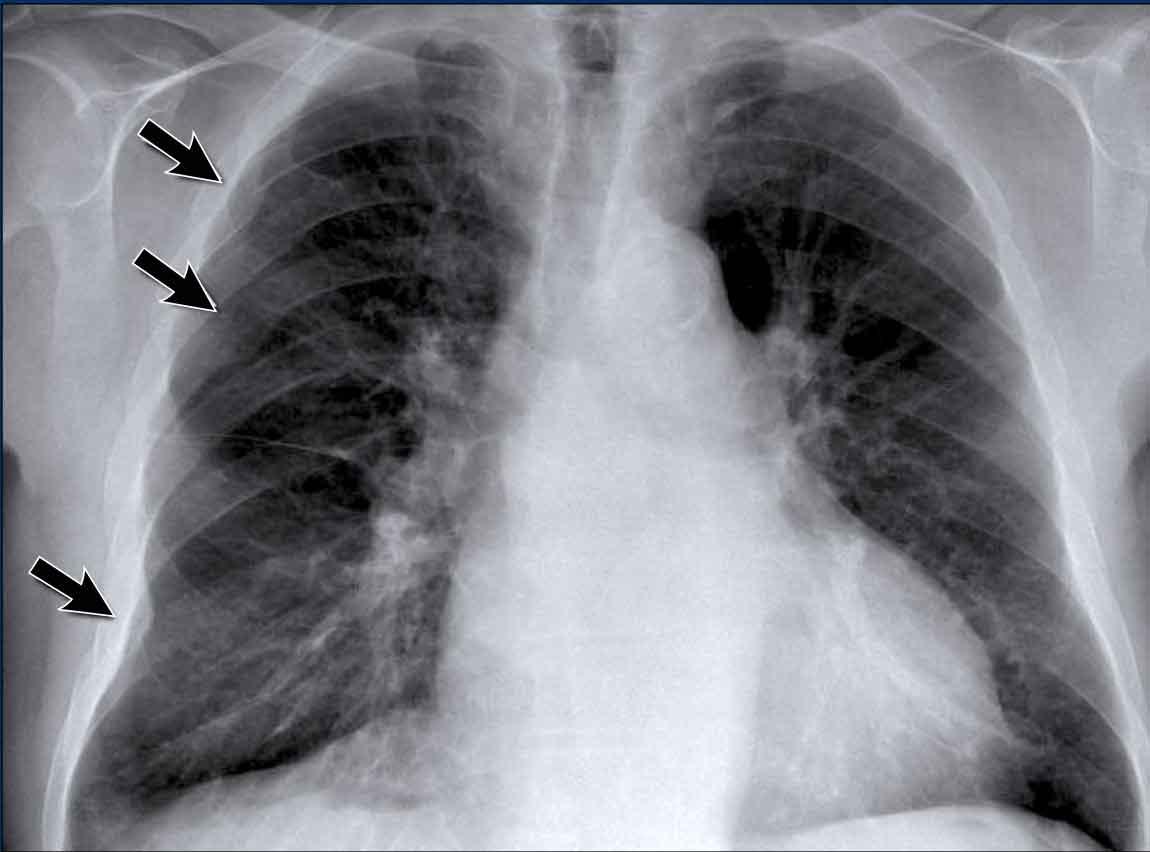

Ca lâm sàng

Bệnh nhân nam 70 tuổi nhập viện sau khi ngã xuống cầu thang, than phiền đau dữ dội vùng hông phải.

Kết quả hình ảnh

- Trên phim X-quang ngực tư thế thẳng (PA), không thấy hình ảnh ngón thứ năm bên phải.

- Trên tư thế nghiêng, có hình ảnh tăng tỷ trọng chiếu lên vùng cột sống ngực dưới.

Chẩn đoán của bạn là gì?

Các dấu hiệu phù hợp với xẹp phổi thùy dưới phải.

Trên tư thế thẳng (PA), lưu ý bờ tim phải có hình dạng bất thường. Động mạch phổi liên thùy phải không được nhìn thấy — do nó không được bao quanh bởi nhu mô phổi thông khí, mà thay vào đó là thùy dưới phải bị xẹp, nằm kề cạnh nhĩ phải.

Trên phim chụp kiểm tra, thùy dưới phải đã nở lại và hình ảnh xẹp phổi đã hồi phục.

Điều này gợi ý rằng xẹp phổi nhiều khả năng là do giảm thông khí sau chấn thương kèm theo nút nhầy.

Cũng ghi nhận trên phim kiểm tra là sự tái xuất hiện của ngón thứ năm bên phải (mũi tên đen) và sự phục hồi bờ tim phải bình thường (mũi tên trắng), xác nhận thùy dưới đã nở lại.